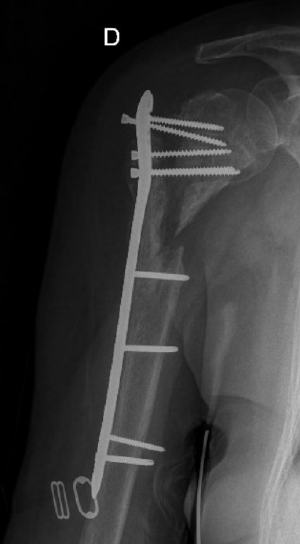

Pre-op

- 81-year-old female patient

- Multiple medical issues

- Fracture of proximal humerus

- 2 years ago > ORIF with plate in Honduras

Poor outcome:

- Very limited function

- Severe pain (8/10)

- Clear non-union

- Suspected infection